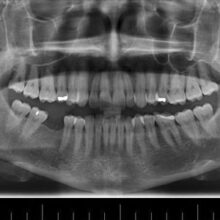

1. Evaluation

First, we need to determine if you are a right candidate for dental implants. To do this, we take impressions, photos, x-rays, CT scans. This will give us information about your bone quality, volume and shape.